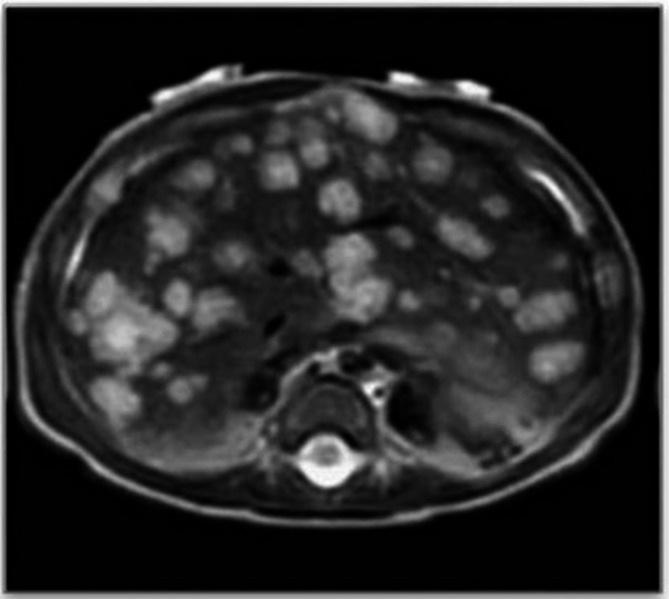

Consumptive hypothyroidism complicating infantile hepatic hemangioma successfully treated with propranolol: a case report and literature review.

普萘洛尔成功治疗小儿肝血管瘤消耗性甲状腺功能减退1例并文献复习。